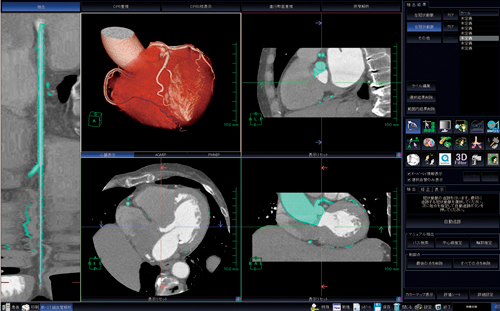

当院では,主にPCIの治療基準の1つとして,またはCABG(coronary artery bypass graft)術の術前・術後に実施し,血行再建の効果を見るために行っている(図6)。

図6 CABG評価

近年,循環器領域における画像診断が飛躍的に進歩している。各検査装置の発展に伴い,画像処理用ワークステーションも発展の道をたどっており,今日の診療にとって必要不可欠の存在となっていると感じる。これらワークステーションを駆使することでより良い医療を提供できるようになると考える。最後に,当院における臨床画像を提示する(図7)。

図7 臨床画像